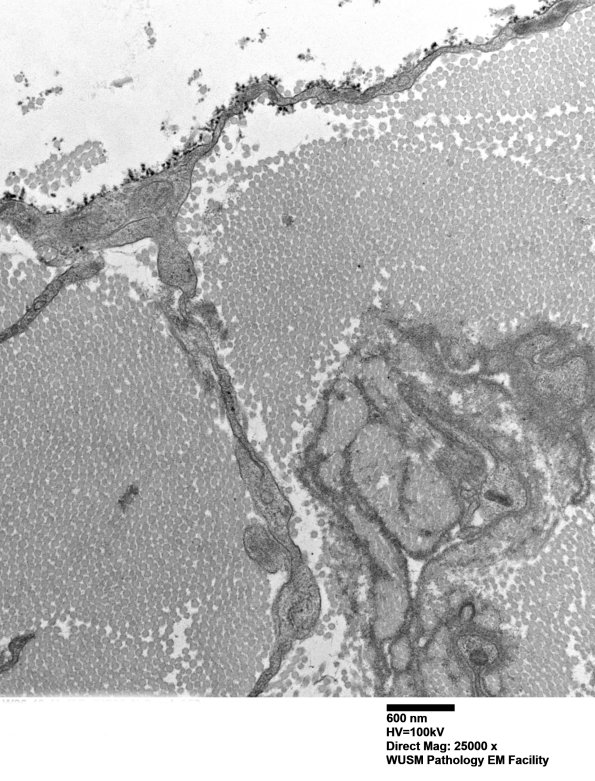

Washington University Experience | PERIPHERAL NEUROPATHY | 4 AXONAL DEGENERATION | 3 Electron Microscopy | 7A5B Chronic Degeneration (Case 33) Sural_052 - Copy

The individual processes in this series of images are hard to establish as Schwannian, fibroblastic or histiocytic. (electron micrographs)